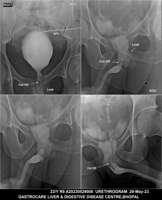

Section: URETHROGRAM

Total: 95 Cases